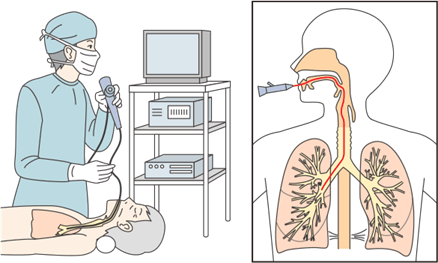

内視鏡検査

内視鏡検査は、口や鼻から気管支鏡を入れて行うものと、胸壁にあけた穴から胸腔鏡を入れて行うものがあります。気管支鏡検査は局所麻酔のみで、外来で行うことができる検査です。胸腔鏡検査は、全身麻酔が必要で患者さんへの負担も大きいため、気管支鏡検査で診断がつかないときに行われることがあります。

気管支鏡とは

気管支鏡とは直径6mm程度のファイバーを鼻あるいは口から挿入し、先端のカメラで気管支の内部を観察したり、肺の組織を採取したりする検査です。かつては全身麻酔で水道管のような太いチューブを使っていましたが(硬性気管支鏡といいます)、日本の池田茂人氏によって気管支ファイバーが開発され、患者さんの負担が著しく軽減され、現在は局所麻酔で行われるようになりました。なお、硬性気管支鏡は検査の目的によっては今でも使われています。

気管支鏡を使った検査は、肺がんだけでなく、肺のさまざまな病気の検査としておこなわれています。気管支の粘膜や気管支がふさがっていないかどうかの観察、病巣の一部を採取、気管支内の異物除去、レーザー照射の治療にも用いられています。

ファイバーを挿入する口あるいは鼻に局所麻酔をかけた後、ファイバーをゆっくりと挿入し、気管や気管支内に局所麻酔液を散布しながら、ファイバーを気管支の奥に進めます。局所麻酔液を散布するのは、咳や異物感を軽くするためです。

気管支鏡検査は、気管支内部の観察だけであれば5分から10分で終了します。

病巣が直接確認できた場合、あるいはX線透視で病巣が確認された場合は、その部分の組織を擦過(擦り取ること)あるいは組織の一部を採取します。組織を採取しても痛みはありません。組織採取時の危険性としては出血があります。通常は10分程度で出血は収まりますが、稀に出血で入院等が必要となることも報告されています。

なお最近では、気管支鏡にカメラだけでなく超音波装置を備え(EBUS)、組織を採取する針のついた装置も開発されており、今までできなかった場所から検体が採取できるようになっています。

口あるいは鼻に局所麻酔を噴霧した後、ファイバーをゆっくりと挿入

気管支鏡の観察写真